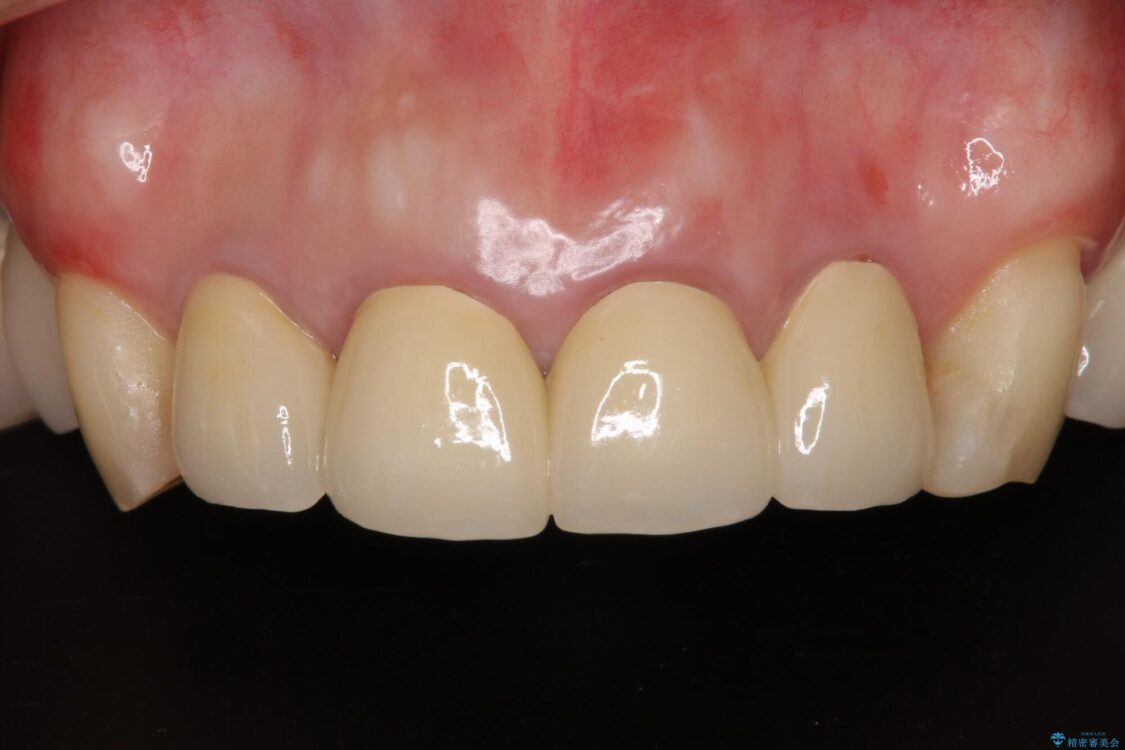

治療後について

日頃の歯磨きをしっかりと行ってくださるので、新しい仮歯に変えてから速やかに歯肉の状態が改善されました。

歯肉からの出血がほとんどないため精度の良い型取りができ、非常に適合の良い補綴治療を行うことができました。

治療後

• 仮歯のまま放置した前歯 オールセラミッククラウンで自然な前歯に 治療後画像